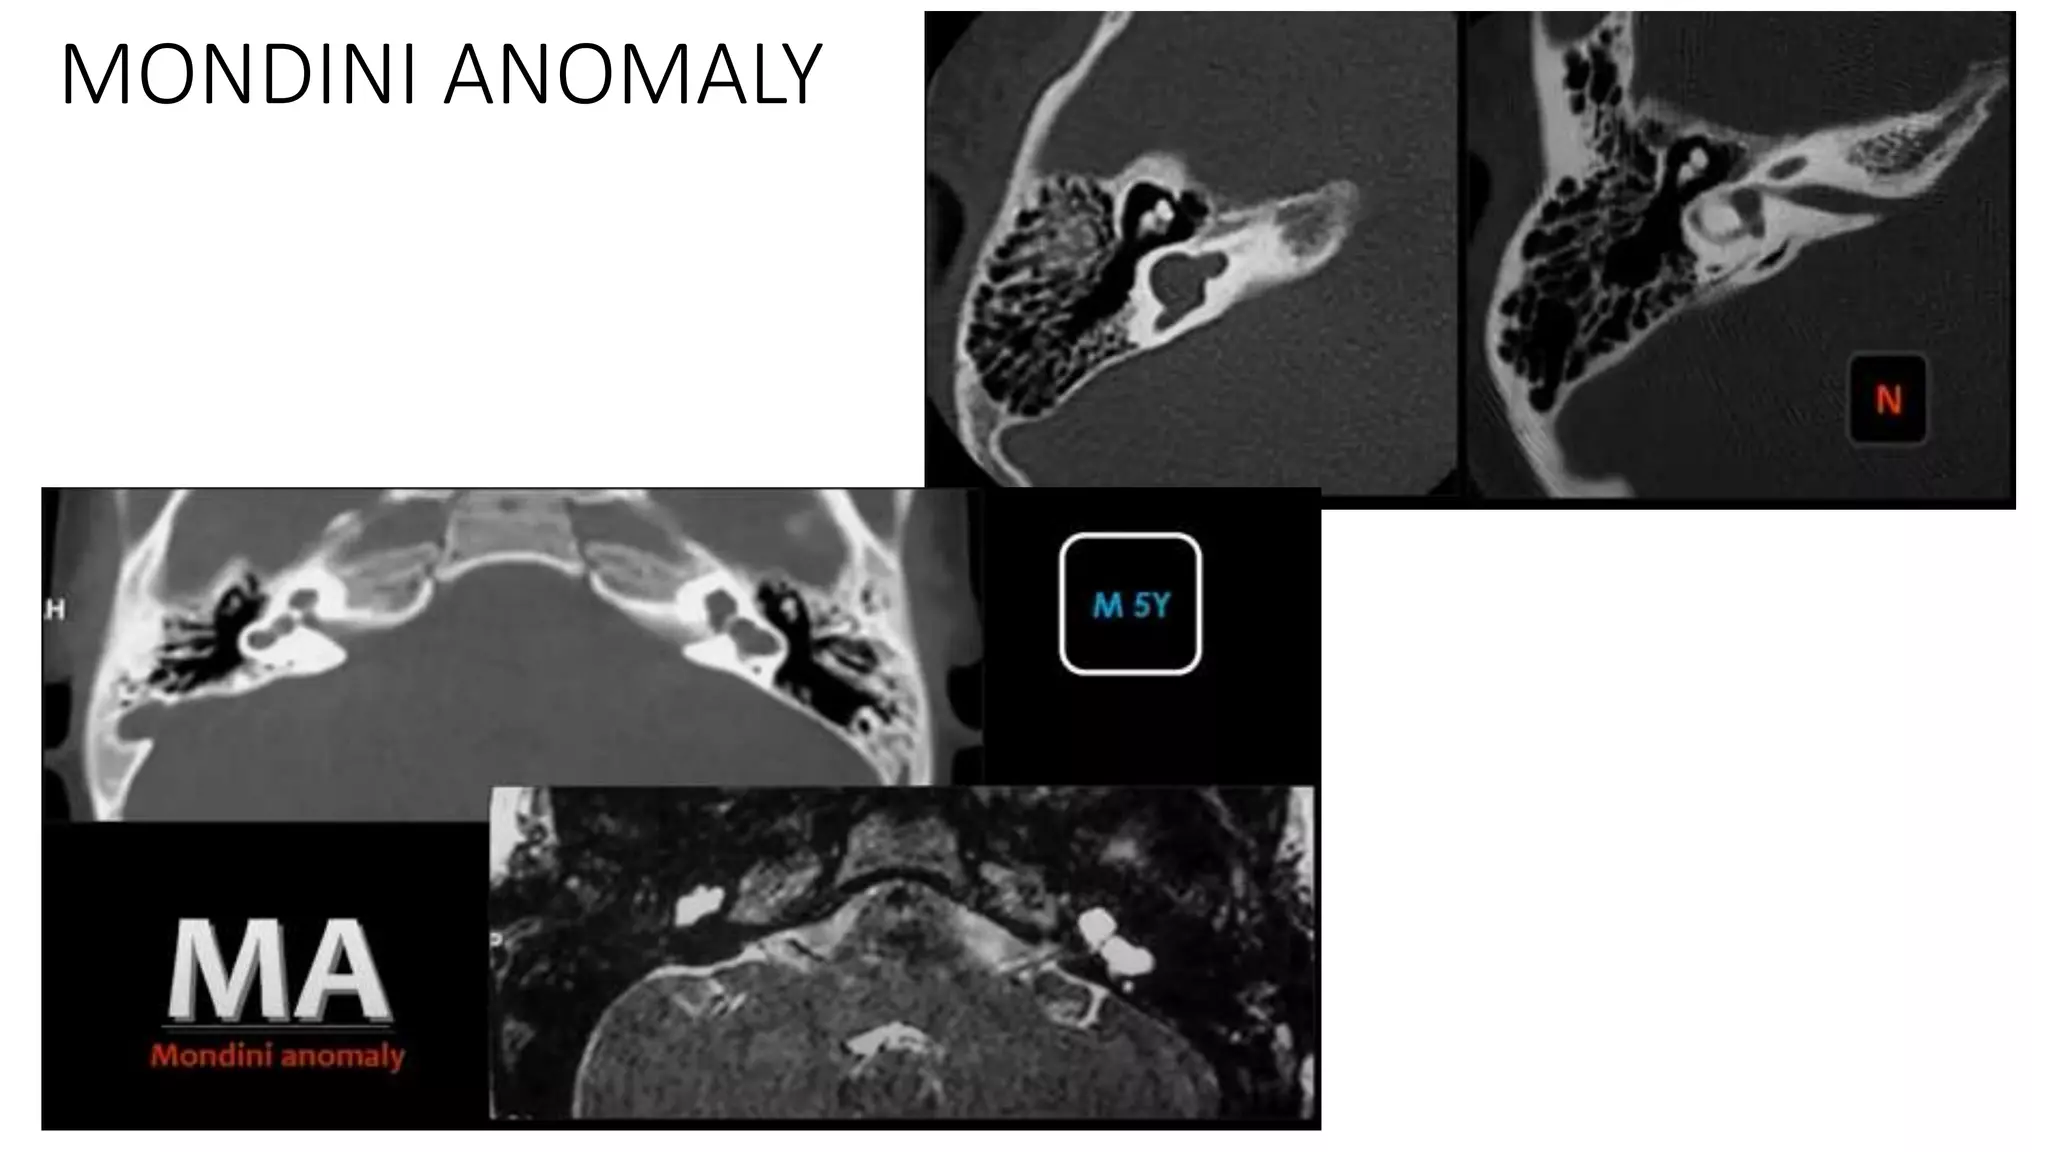

MONDINI ANOMALY

Ice-cream cone appearance in CT and MRI

Axial 3D FIESTA showing dilated endolymphatic duct on

both sides

Cochlear ossification on both sides

Narrowed IAC on either side with absent B/L VCN complex